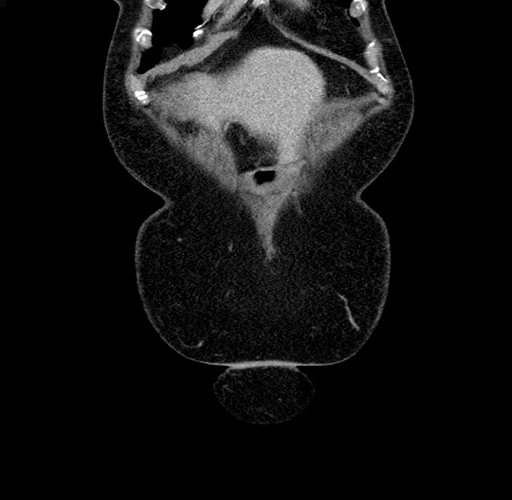

Pre-Chemo: Coronal Venous